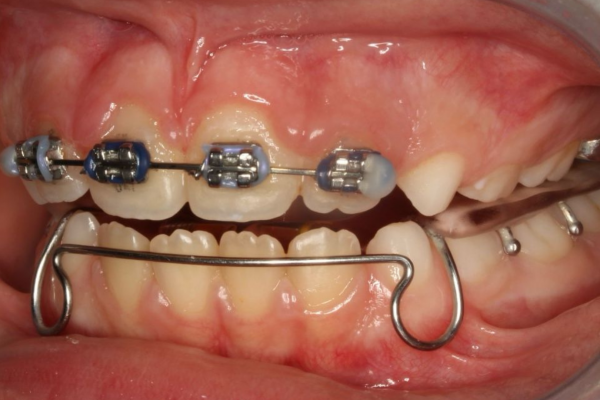

Cada paciente y cada tratamiento es único. El profundo conocimiento de la anatomía y de nuestros pacientes junto con la tecnología más avanzada nos permite realizar diagnósticos certeros. Localizando el origen del problema muchas veces incluso antes de que se produzca evitando así su aparición.

con ortopedia y ortodoncia, paso a paso.